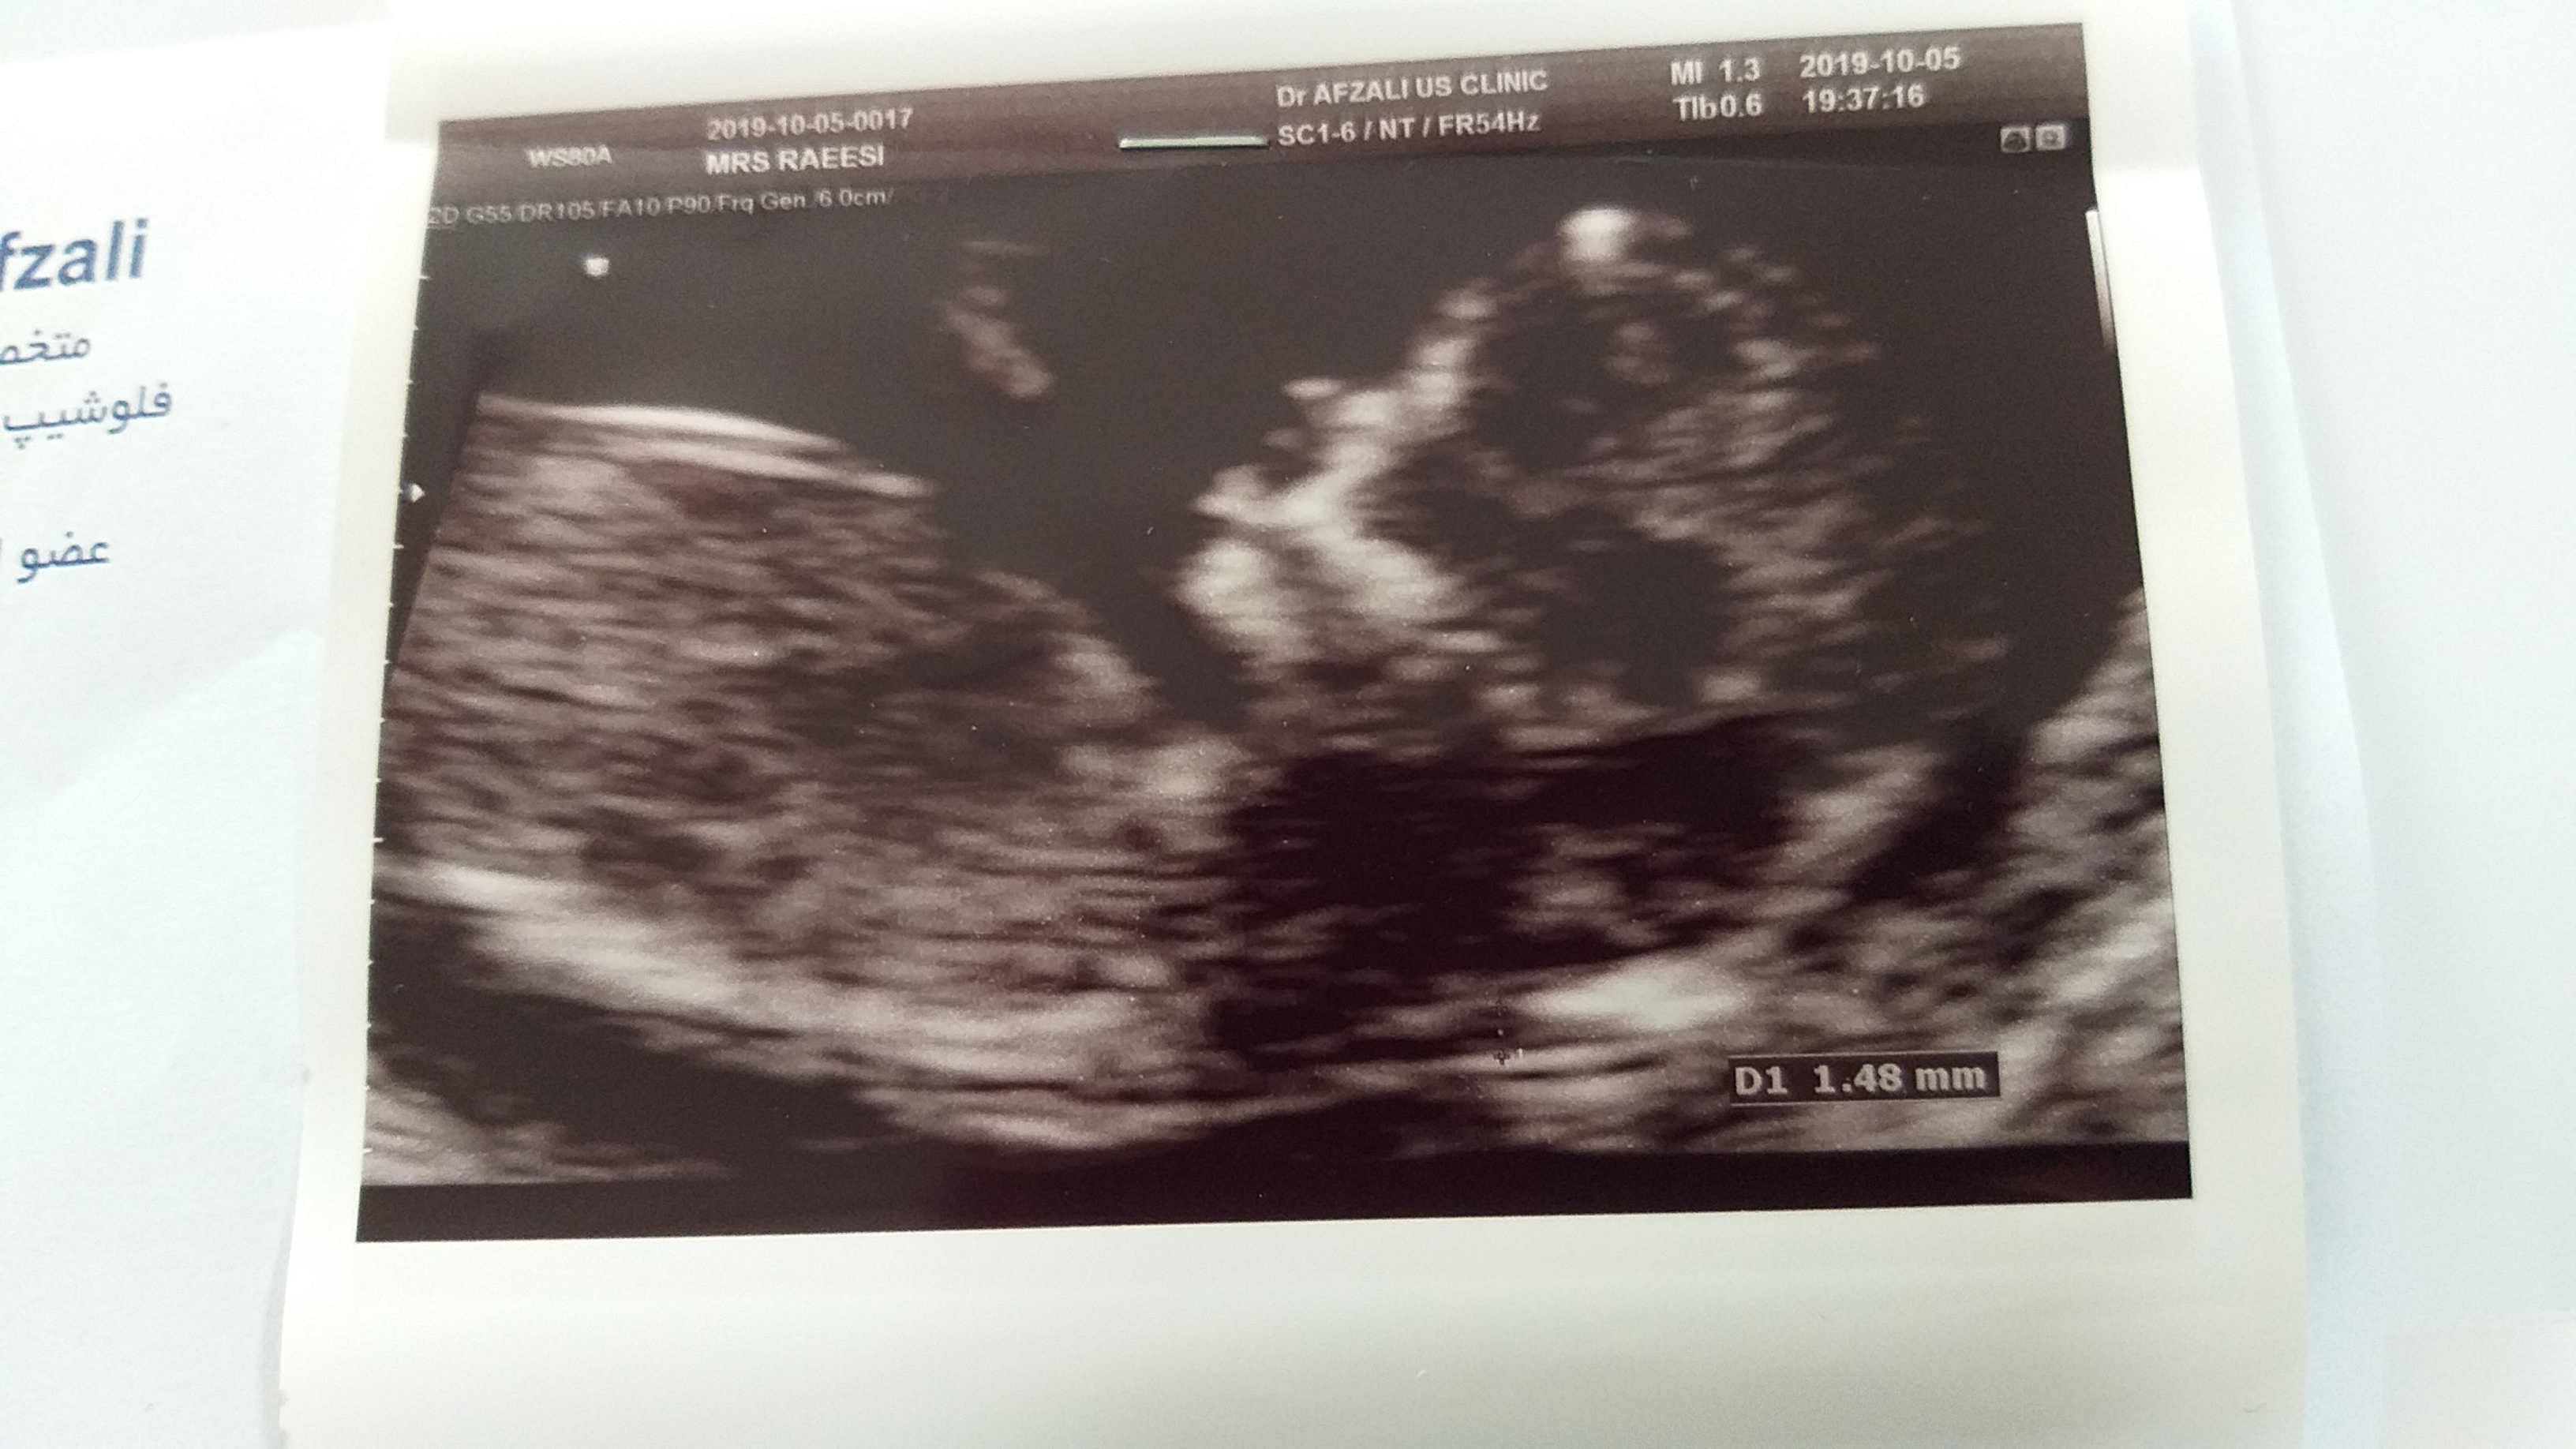

سلام خاله جونی من دقیقا ۱۲ هفتمه😊

عزیزم اگه عکس کاملشو میفرستادی دقیق میتونستم بهت بگم ولی اینجا دنبالچه اش نیافتاده واز روی جمجمه پنجاه درصد پسره

ممنون عزیزم که وقت گذاشتی😘دکتر همین یه عکسو بهم داد.راستی جنسیت دوقلوهای شما مشخص شد؟

آهان ممنونم ،فک کردم بااون یکی خانوم بودی ،دقیقا غربالگری هم بهم گفت احتمال ۷۰ پسره